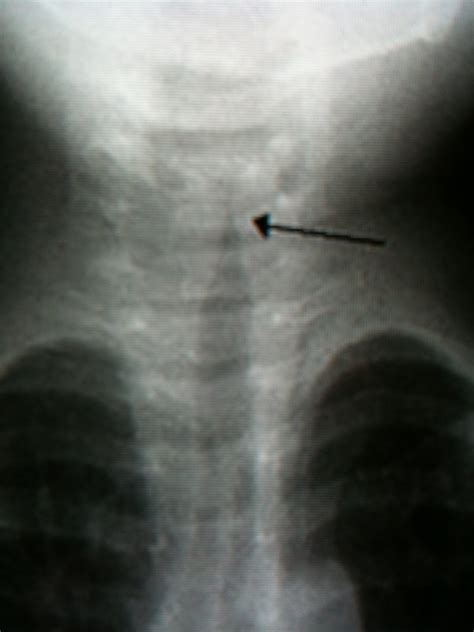

The Steeple Sign Croup is a specific finding observed on a frontal chest or neck X-ray. When a child with suspected croup undergoes imaging to rule out other, more serious causes of airway obstruction, radiologists look at the column of air within the trachea.

Normally, the trachea appears relatively straight on an X-ray. However, in cases of significant subglottic inflammation (swelling just below the vocal cords), the air column becomes narrowed. On the X-ray, this narrowing creates a shape that resembles the sharp, pointed roof of a church steeple, hence the name Steeple Sign.

It is important to note that this sign is radiographic—it is seen on imaging, not by looking at the child. Furthermore, not every child with croup will demonstrate the steeple sign on an X-ray, and not every child with croup requires an X-ray to be diagnosed.